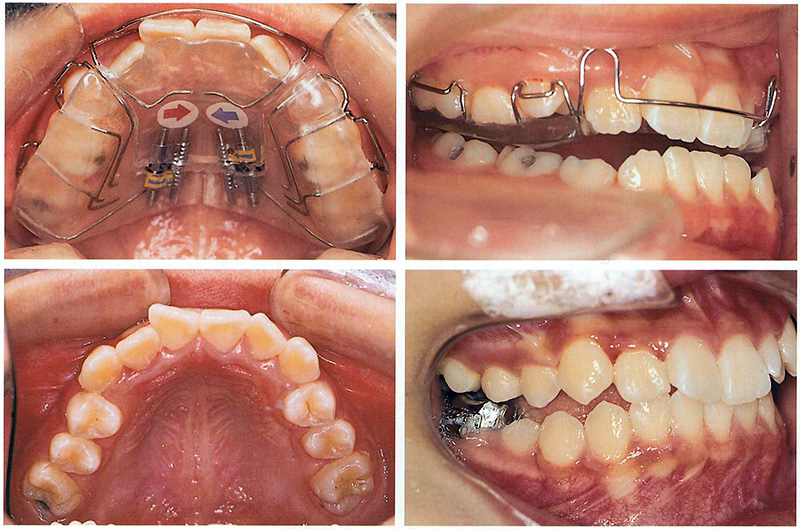

위 환자의 경우 왼쪽 송곳니가 내려올 공간은 부족하고 오른쪽 앞니도 안으로 들어가서 나와 반대로 물리고 있었습니다. 그리고 오른쪽 두번째 작은 어금니 또한 앞뒤 치아에 걸려서 내려오지 못하고 있었습니다. 물론 나중에 성인이 된 이후에 교정을 해도 되겠지만(발치 교정을 해야 할 가능성이 높아지겠죠), 커서 복잡한 치아 교정을 안해도 될 수 있도록 다른 치아들이 맹출하기 전에 미리 공간을 만들어주기로 하였습니다.

치과대학에서 원내생 실습을 하는 동안 가철성 교정장치를 만드는 실습을 하는데, 그 때 점수도 가장 높고 가장 만들기 어려운 장치가 하나 있었는데요... 바로 이런 케이스를 교정해주기 위한 "sagittal appliance" 입니다. 이 장치의 역할은 송곳니가 맹출할 수 있는 공간을 확보하기 위해 앞니는 앞으로 밀어주고, 어금니는 뒤로 밀어주는 장치입니다.

위 환자의 경우 안으로 들어와있는 앞니도 밀어주고 공간이 부족해서 나오지 못하고 있는 작은 어금니 공간도 마련해주기 위해 sagittal appliance에 앞니를 밀어주기 위한 push spring과 작은 어금니 공간을 마련해주기 위한 distal screw도 추가해주었습니다. 이 정도면 10점짜리 최고난이도 장치가 아닐까 싶습니다 ^^;;

아래 사진은 위 환자와 비슷한 케이스로, 치과교정학 교과서에 나오는 사진을 발췌한 것입니다. 양측에 공간이 부족하여 나오고 있지 못한 송곳니 공간을 만들어주기 위해 sagittal appliance를 착용하였고, 그 결과 드라마틱하게 송곳니가 모두 맹출하였고 거꾸로 물리던 앞니도 교정되었습니다. 이런 가철성 장치 교정을 어렸을 때 해주지 않았다면, 커서 발치 교정을 했어야 했을 케이스였습니다.